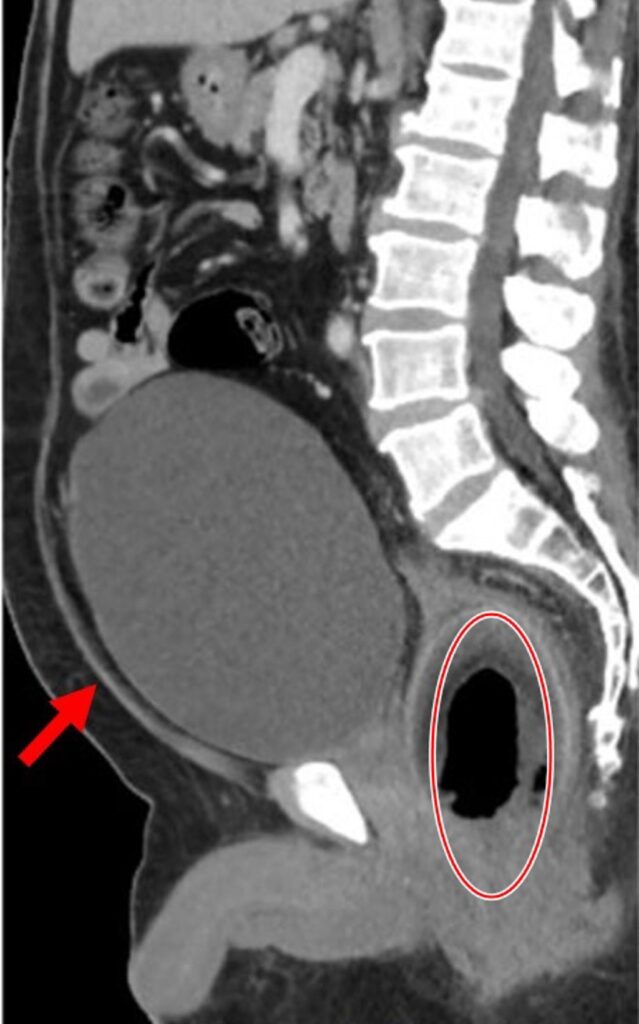

<p>這名56歲男性患者，到院的時候主訴腹痛已經2天了，而且尿不出來合併嚴重便祕。經理學檢查顯示，患者生命體徵穩定，但腹部膨脹，壓痛還有反彈痛。透過電腦斷層掃描顯示，患者直腸內有一個巨大、略帶空心的圓形異物，壓迫到攝護腺和尿道，已經把他整個輸尿管阻塞住了，導致尿滯留。</p>

<figure class="wp-block-image size-large"><img loading="lazy" decoding="async" width="639" height="1024" src="https://wellnews.media/wp-content/uploads/2024/03/358-639x1024.jpg" alt="" class="wp-image-10513" srcset="https://wellnews.media/wp-content/uploads/2024/03/358-639x1024.jpg 639w, https://wellnews.media/wp-content/uploads/2024/03/358-187x300.jpg 187w, https://wellnews.media/wp-content/uploads/2024/03/358-768x1230.jpg 768w, https://wellnews.media/wp-content/uploads/2024/03/358-959x1536.jpg 959w, https://wellnews.media/wp-content/uploads/2024/03/358-696x1115.jpg 696w, https://wellnews.media/wp-content/uploads/2024/03/358-262x420.jpg 262w, https://wellnews.media/wp-content/uploads/2024/03/358.jpg 1024w" sizes="(max-width: 639px) 100vw, 639px" /><figcaption class="wp-element-caption"><strong>透過電腦斷層，可以看到被塞進肛門的椰子滑到直腸深處。（圖/義大醫院提供）</strong></figcaption></figure>